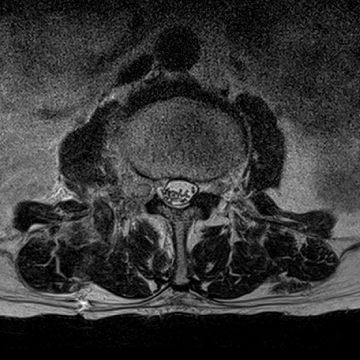

허리 디스크 수술 전·후

2022.08.01

2022.08.04

ㆍ환자 동의를 받은 자료이며, 이미지 사진은 실물과 다를 수 있습니다.

ㆍ모든 자료는 새움병원 자료입니다.